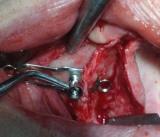

la basale outre la mise en charge immédiate peut aussi se gérer en ostéointégration classique , ex: ce matin petit coup de mou de la patiente , intervention interrompue à l'hémie arcade et reprise ultérieurement

Copie de 398 mqia6r - Eugenol

Copie de 638 qxtxo7 - Eugenol

Copie de 643 sb8onb - Eugenol

Copie de 673 f0ekor - Eugenol